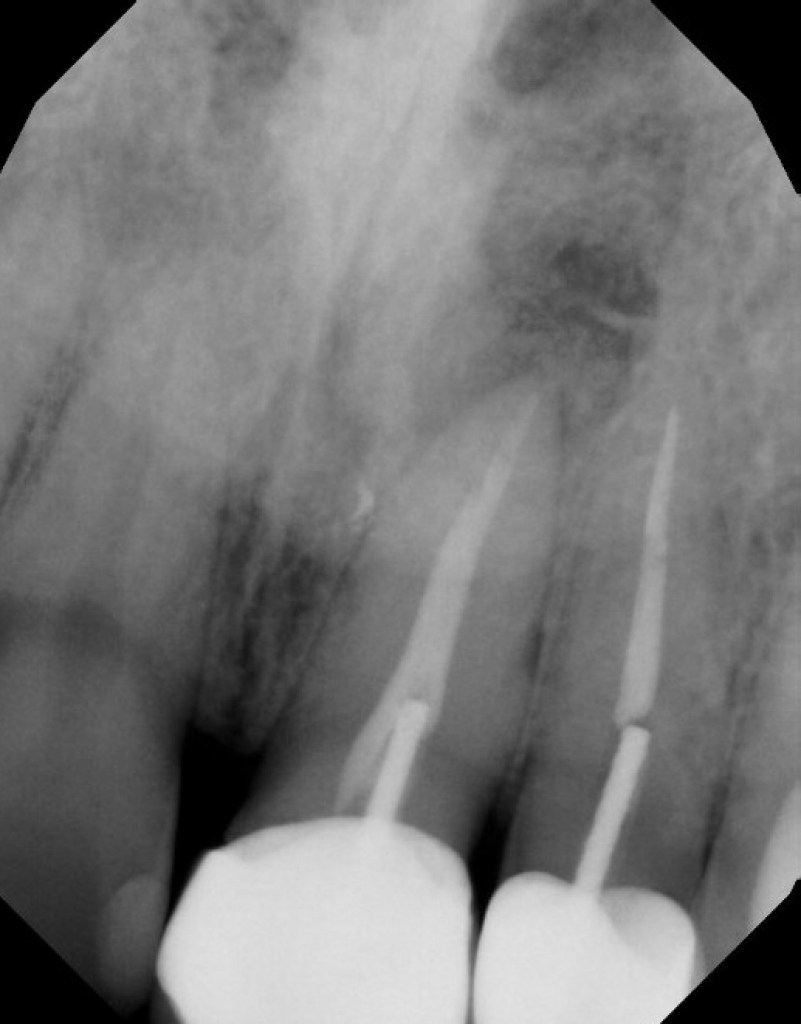

#7 NS-RCT (with SI retrieval)

Dx: Previously Initiated with CAA